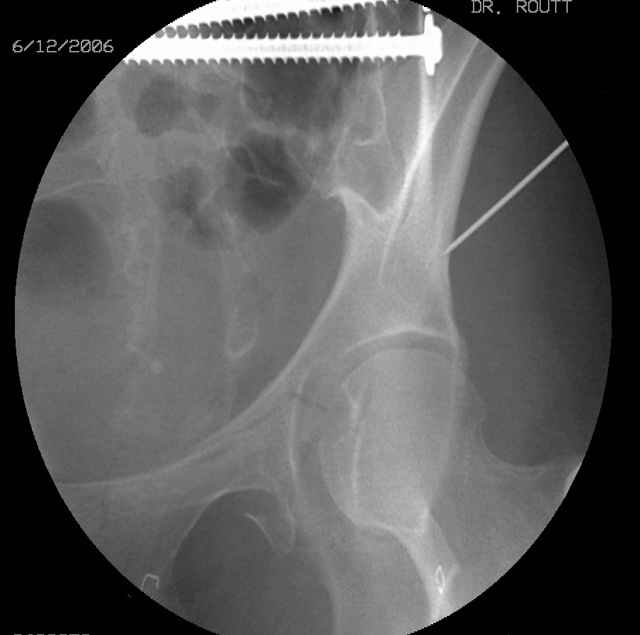

Prone Inlet

OK, now we're inserting the drill percutaneosuy using a sleeve. This fluoro shot is not for this patient (notice no clamp) but I was too lazy to go searching the PACS for one with the clamp on, so pretend...I'll save the next ones and send along...the imaging is the same and the clamp doesn't obstruct imaging other than very rarely...you can always tilt the C-arm a bit to clear it if the clamp obstructs the exact spot that you'd like to see. We'll assume that everyone knows the safe zone for a medullary ramus screw. Use a calibrated drill and sleeve of known length to simplify your life...or use Alex's fancy cannulated screws...I like 3.5mm screws because the oscillating 2.5mm drill bounces and remains intraosseus when it oscillates and contacts endosteal cortical ramus... so will the screw, and like a long bent screw IF the fracture is clamped... if unclamped, when the screw contacts the endosteum, it pushes the reduction apart instead of bouncing. The big 7mm cannulated screws fit few patients and extrude...we very rarely use them any more...you'll see an old one later.